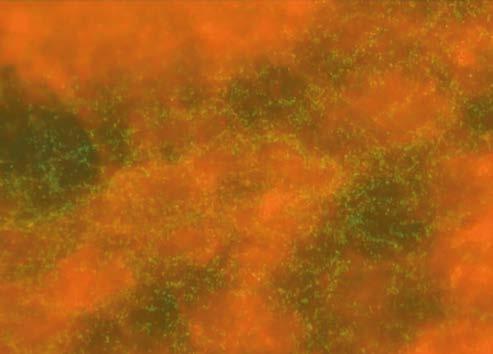

Similarly to MIC results, superior effectiveness of linden and heather honeys was observed in the assessment of antibiofilm activity. Linden honey led to a reduction in biofilm by 54–67% after 4 hours of exposure, while heather honey showed a reduction at the level of 45–58%. Buckwheat and multifloral honeys exhibited much weaker antibiofilm effects, with their biofilm reduction below 20% (Figure 1).

A C Control B D

Figure 1. Antibiofilm activity of Polish honeys against Pseudomonas aeruginosa after 4 hours of exposure. A) Linden honey; B) Heather honey; C) Buckwheat honey; D) Multifloral honey

was conducted for only 4 hours, meaning it was not mature and could be more susceptible to the compounds present in honey. In antibiofilm studies of Portuguese heather honey [27], a different methodology was applied, examining the logarithmic reduction in colony count. A 50% honey concentration led to approximately 50% decrease in the logarithm of colony count.